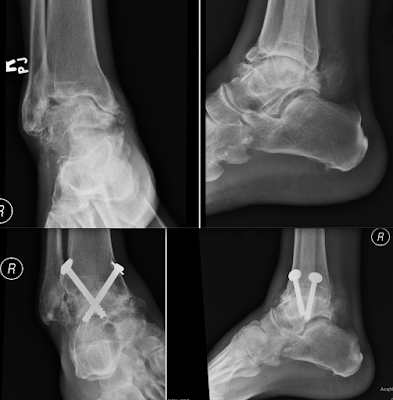

Arthroscopic Ankle Fusion Cases

Case 1 - Pre-op, 6 months post-op